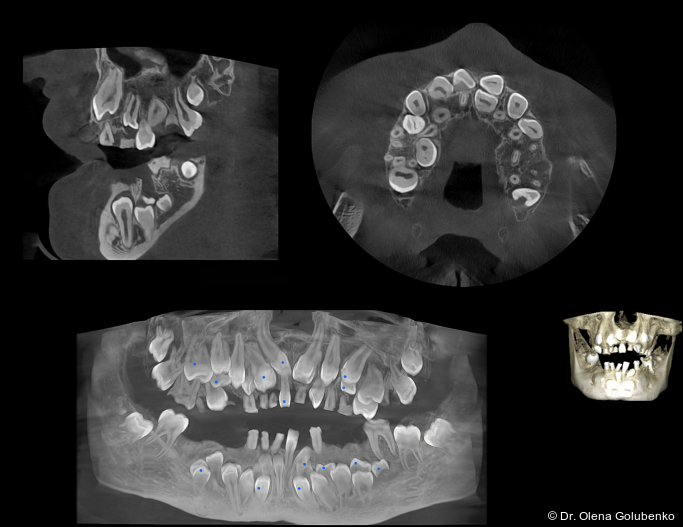

Die dreidimensionale Bildgebung zeigt meist eine hohe Anzahl nicht durchgebrochener permanenter und überzähliger Zähne, die in unterschiedlicher Lage im Kiefer verbleiben (Abb. 3+4).

Die Diagnostik der cleidokranialen Dysplasie basiert auf einer sorgfältigen klinischen Untersuchung, der Analyse von Panoramaaufnahmen sowie insbesondere auf der digitalen Volumentomografie (DVT). Ziel ist es, die Anzahl, Lage, den Entwicklungsstand sowie mög­liche Interferenzen der retinierten und überzähligen Zähne präzise zu erfassen und in ei­nen funktionellen sowie skelettalen Kontext einzuordnen (Abb. 5–8).